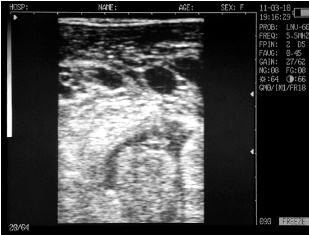

Ovary cows in mid-cycle